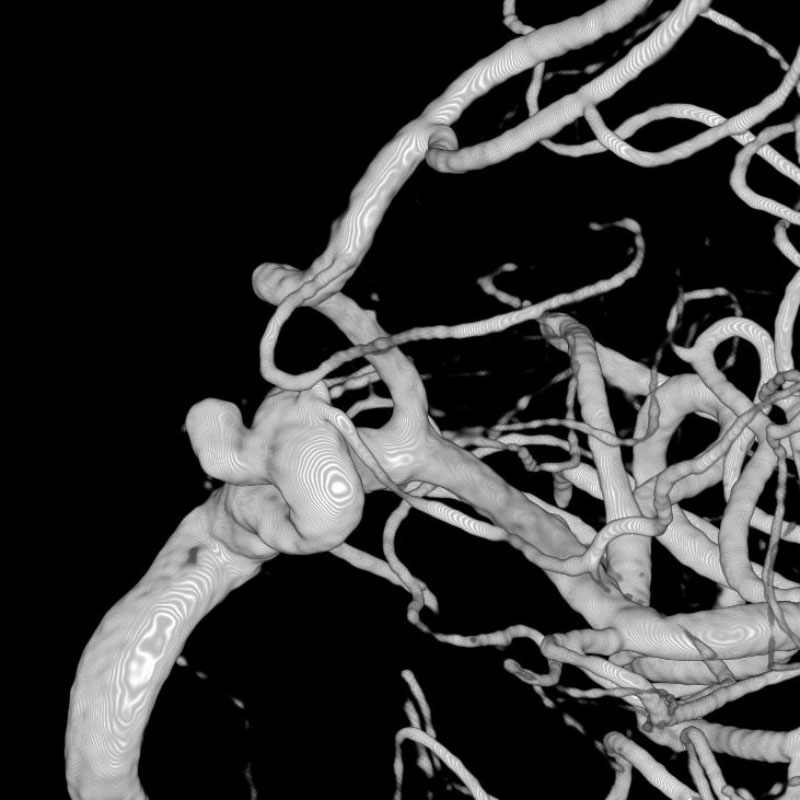

脳動静脈奇形

血管塞栓術

芝野/古谷

脳動脈瘤(Acom)

脳血管内手術

芝野/古谷/木本